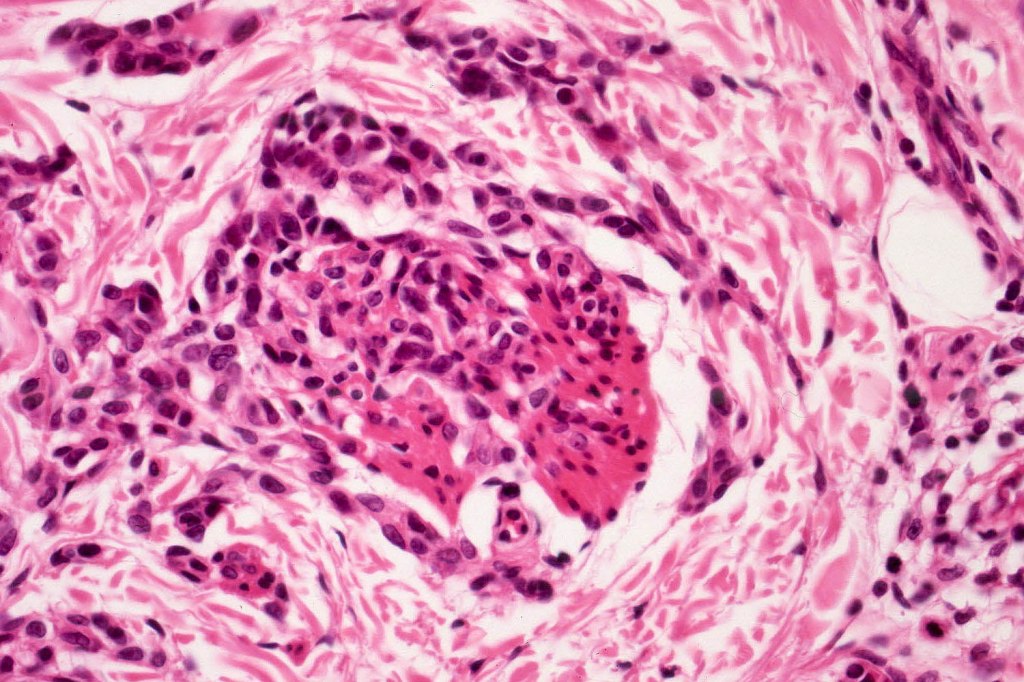

This melanoma arose in a small congenital nevus of the scalp. It metastasized widely. Varying features in different fields.

•Develop in the dermal component

•Typical melanoma, nevoid melanoma, small cell melanoma, pleomorphic/anaplastic melanoma, melanoma with heterologous differentiation & malignant nerve sheath-like melanoma.